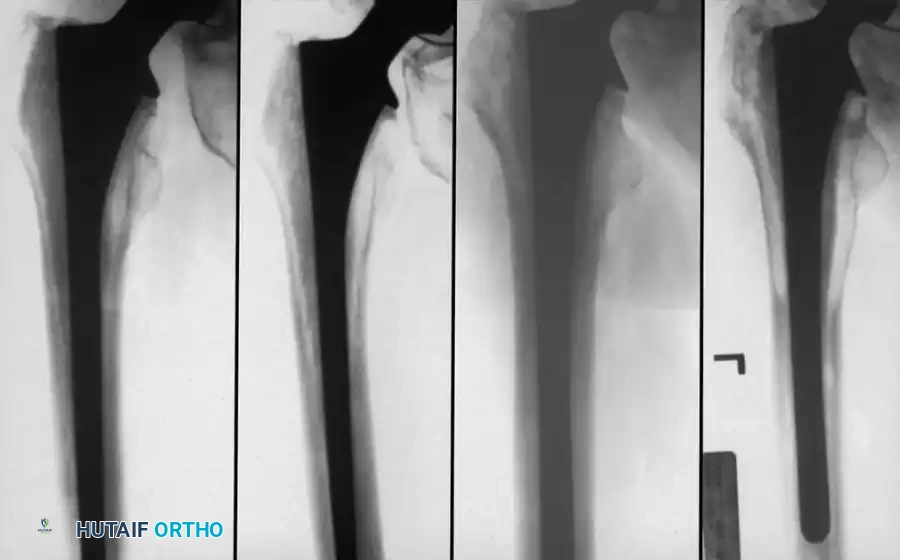

Associated Surgical & Radiographic Imaging